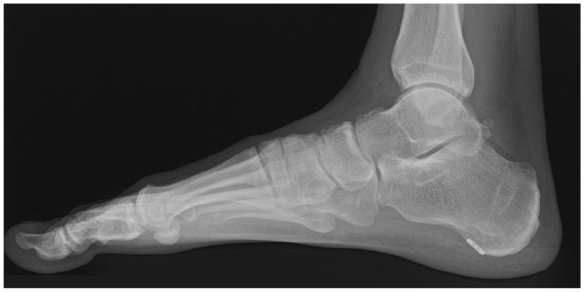

Abstract Image